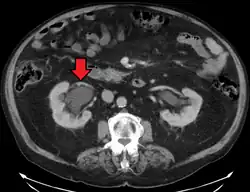

Stone causing hydronephrosis[13]